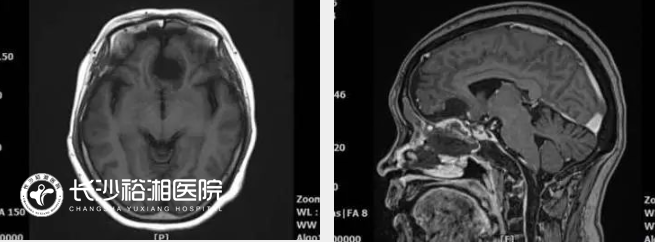

顱底腦膜瘤專指位于顱底部位的腦膜瘤,根據(jù)部位可以分為前顱底腦膜瘤、中顱底腦膜瘤和后顱底腦膜瘤,臨床上常常包括嗅溝腦膜瘤、鞍結(jié)節(jié)腦膜瘤、前床突腦膜瘤、蝶骨嵴腦膜瘤、巖斜區(qū)腦膜瘤和枕骨大孔腦膜瘤等。由于位置深,累及或包裹鄰近的基本神經(jīng)血管結(jié)構(gòu)(如關(guān)鍵動(dòng)脈、顱神經(jīng)、靜脈和靜脈竇),并且在診斷前通常體積較大,顱底解剖復(fù)雜,血管神經(jīng)走行復(fù)雜。盡管多模式治療策略隨著立體定向和分割放療的進(jìn)展而不斷發(fā)展,但手術(shù)切除仍然是治療這些腫瘤的主要方法。然而,從技術(shù)角度來看,切除這些腫瘤是具有挑戰(zhàn)性的,需要幾種顱底手術(shù)方法的專業(yè)知識(shí),這些手術(shù)方法依賴于充分的骨切除,最大限度地減少腦回縮,并尊重附近的神經(jīng)血管結(jié)構(gòu)。顱底外科組長(zhǎng)期從事顯微外科微創(chuàng)手術(shù),對(duì)于顱底各類腫瘤具有豐富的微創(chuàng)治療經(jīng)驗(yàn)。